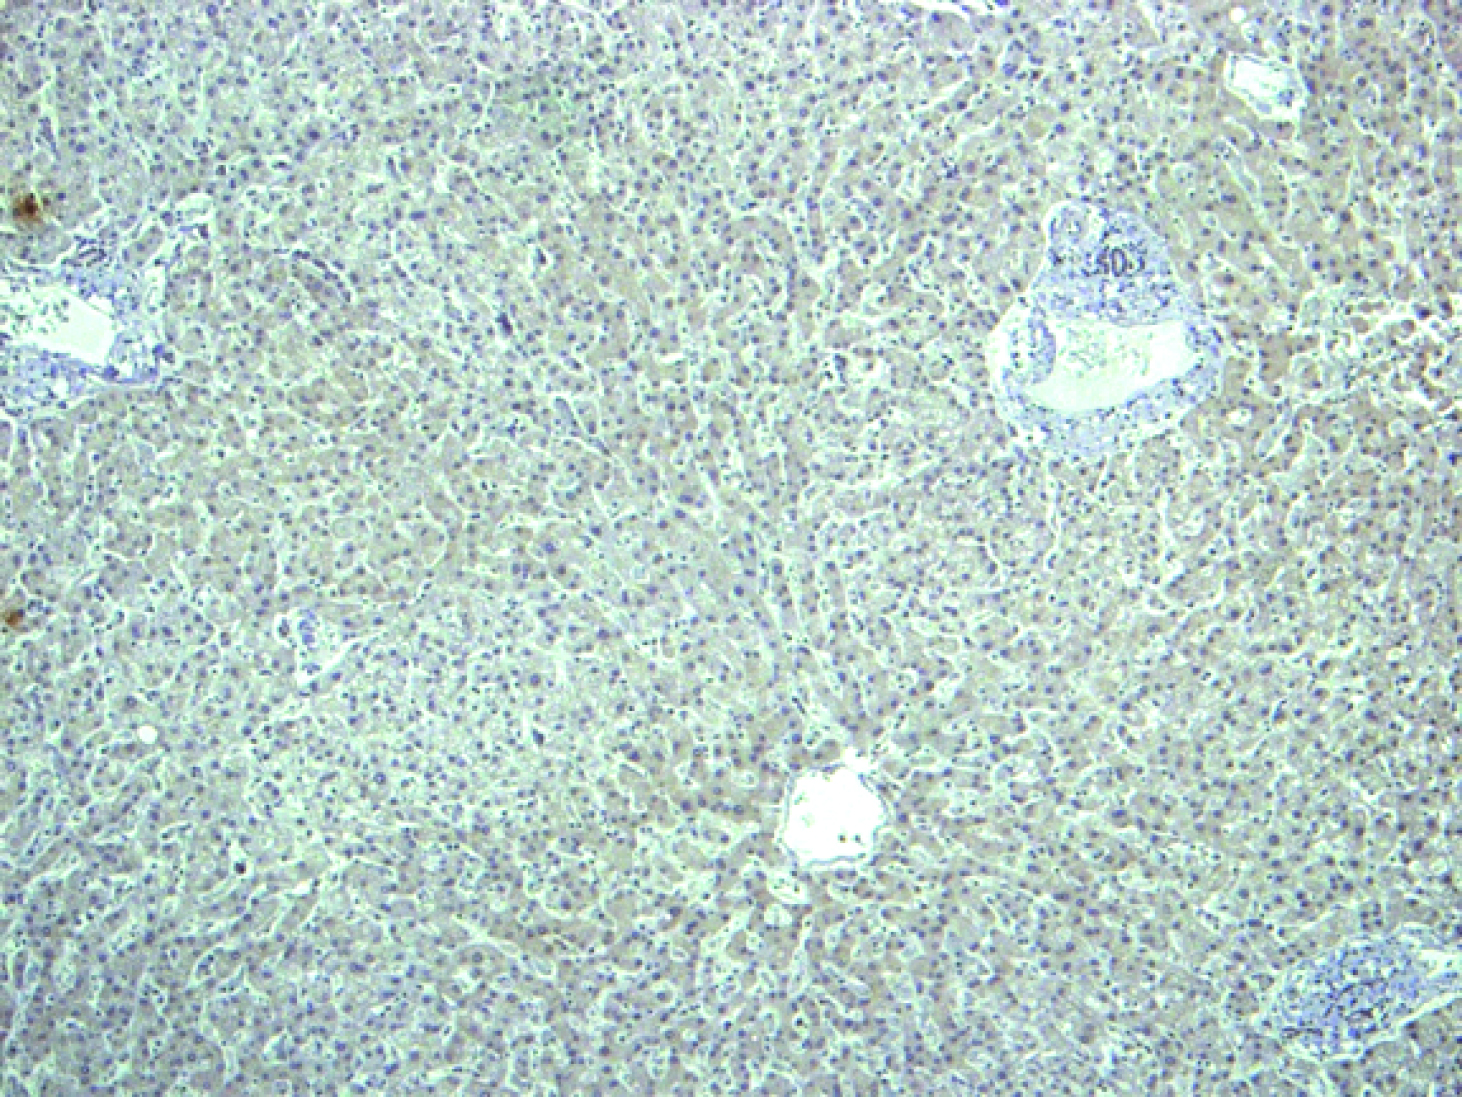

“The best thing about the study is that we demonstrate that the development of pathological blood vessels can be stopped by interfering with CPEB4 proteins while positive vascularisation remains intact,” says Méndez. The experiments in cells in vitro, in animal models, and in samples taken from patients with cirrhosis have revealed the molecular mechanisms through which the increase in CPEB4 favours the overexpression of VEGF in cirrhosis.